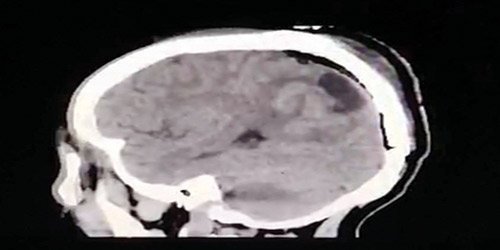

نجح فريق طبي متخصص بجراحة المخ والأعصاب بمستشفى الملك فهد العام بالمدينة المنورة في إزالة ورم من دماغ معتمر يبلغ من العمر 44 عاماً، وكان المريض يعاني من صداع شديد، وتشنجات وضعف بالجزء الأيسر من الجسم وتغير في مجال الرؤية حيث تم على الفور عمل أشعة مقطعية أظهرت وجود كتلة في الجزء الخلفي الأيمن من الدماغ، وقد تم تنويمه وعمل أشعة مغناطيسية للرأس بينت وجود كتلة كبيرة خارج الدماغ تسببت بضغط على الدماغ أدت إلى ارتشاح بالدماغ وهذه الكتلة غالباً ما تكون حميدة.

وبعد استكمال الفحوصات الطبية والتحاليل المخبرية تمت عملية استئصال الكتلة بشكل كامل عن طريق جراحة دقيقة باستخدام الميكروسكوب واستمرت لأكثر من 8 ساعات تكللت بالنجاح ولله الحمد، وتم تحويل المريض للعناية المركزة لمدة يوم واحد قبل أن يقضي ثلاثة أيام في أقسام التنويم للمتابعة وإعادة التأهيل حتى غادر المستشفى بصحة جيدة وتحسن كبير ولله الحمد.